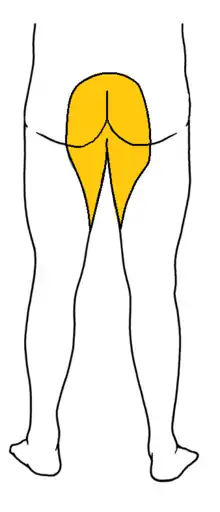

- Saddle anesthesia (see diagram), i.e., anesthesia or paraesthesia involving S3 to S5 dermatomes,[6]: 26 including the perineum, external genitalia and anus; or more descriptively, numbness or "pins-and-needles" sensations of the groin and inner thighs which would contact a saddle when riding a horse.